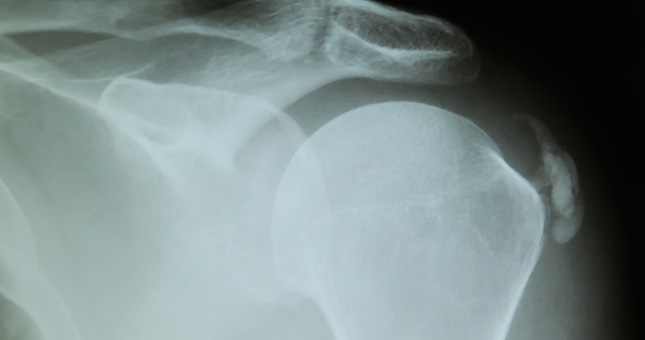

Calcificaciones

Es un proceso en el cual el calcio se acumula en el tejido del tendón, haciendo que dicho tejido se endurezca. Produciendo dolor al movimiento. Puede ser más o menos grande.